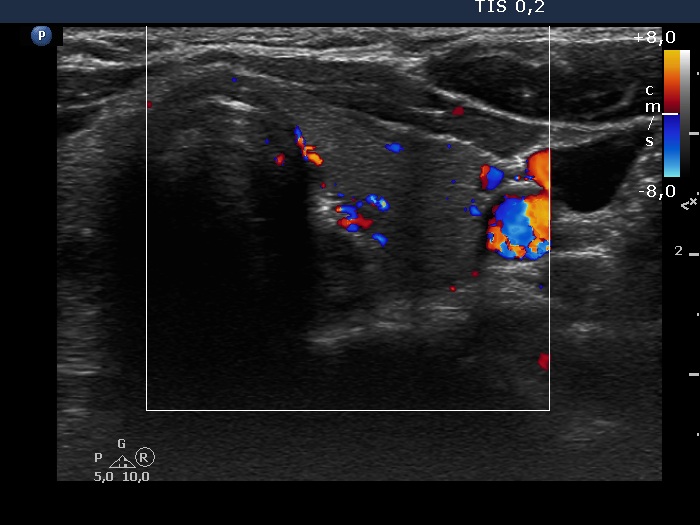

Left lobe, transverse view, color Doppler mode. The vascularization is average.